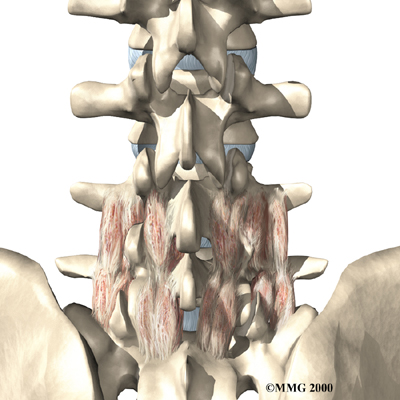

Posterior Lumbar Fusion

Lumbar disc herniation causes mechanical pain, the type of pain caused by wear and tear in the parts of the lumbar spine. Fusion surgery is mainly used to stop movement of the painful area by joining two or more vertebrae into one solid bone. This keeps the bones and joints from moving, easing mechanical pain.

In posterior lumbar fusion, the surgeon lays small grafts of bone over the problem area on the back of the spinal column. Most surgeons will also apply metal plates and screws to prevent the problem vertebrae from moving. This protects the graft so it can heal better and faster.

Related Document: FYZICAL North Richland Hills Guide to Posterior Lumbar Fusion